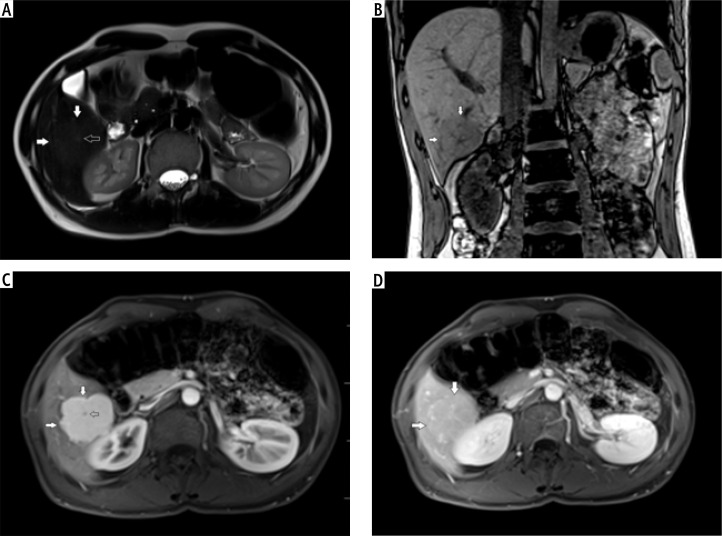

Aim of the study: Hepatocellular adenoma (HCA) and focal nodular hyperplasia (FNH) are benign liver tumors. Hepatocellular adenoma has potential for growth, metaplasia and rupture; therefore, it should be monitored long term. In the current guidelines biopsy is not recommended in the standard diagnostic protocol. Magnetic resonance imaging (MRI) is accepted as standard in diagnostics and monitoring of these lesions. The aim of the study was to compare contrast-enhanced ultrasound (CEUS) and MRI in imaging of these tumors and determine whether CEUS can be useful in monitoring benign liver tumors.

Material and methods: A retrospective analysis of 47 patients with HCA (32 tumors) and FNH (27 tumors) was carried out. A comparison between MRI and CEUS in predicting malignant transformation was performed.

Results: A similar tumor enhancement profile to unchanged liver parenchyma was observed in both groups. The difference in the arterial phase was on average up to 30 dB. After 20-30 s, the enhancement of HCA and FNH in relation to the liver parenchyma was similar (difference up to 4-5 dB). Homogeneity and equalization of the tumor to background enhancement was observed until the end of the examination. The discriminative feature is the presence of a non-contrasting central fibrous scar observed in both imaging methods in the FNH group.

Conclusions: CEUS can be a promising method in monitoring focal liver lesions due to low cost and low risk of complications. It is essential to analyze the early arterial phase up to 30 s to demonstrate homogeneous enhancement of the tumor and potential presence of a wash-out effect during later phases of examination.